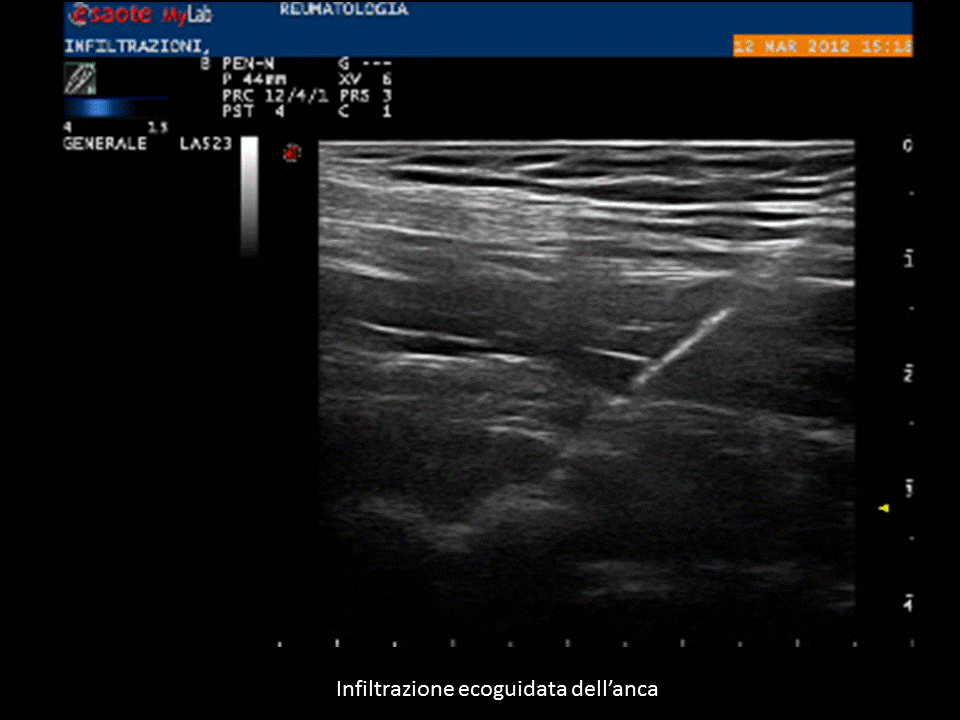

Sempre recentemente è stato ampiamente dimostrato che, soprattutto per le articolazioni profonde, risulta molto difficile andare a posizionare l’ago e quindi il farmaco nella zona giusta, per cui si è fatto sempre più strada il concetto che le infiltrazioni necessitano di una guida ecografica.

Ciò è particolarmente vero per l’anca, dove si è visto che senza guida ecografica solo una minima parte delle infiltrazioni arriva realmente a destinazione.

Le procedure ecoguidate, oltre a garantire un corretto raggiungimento della struttura bersaglio, permettono di creare minor discomfort al paziente e di evitare di colpire strutture nobili durante il tragitto dell’ago. Ovviamente per l’esecuzione di tali procedure è necessario una buona esperienza sia nell’ambito dell’ecografia muscoloscheletrica che in quello delle procedure infiltrative, oltre ad una estrema attenzione al corretto mantenimento di sterilità durante l’operazione.